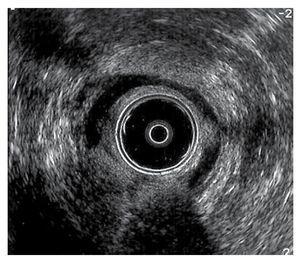

Caso 1. Hombre de 34 años de edad con antecedente de hemorroidectomía tipo Ferguson seis meses previos a su padecimiento, que inició con incontinencia a gases y materia fecal líquida con una frecuencia de tres veces al día. Asimismo, refería escurrimiento de materia fecal líquida de predominio nocturno. Recibió tratamiento con laxantes de volumen y loperamida (2 mg, tres veces al día) durante dos meses, sin mejoría de su sintomatología. Se le realizó un ultrasonido endoanal de 360o, en donde se observó una lesión anterior del esfínter interno (Figura 1). En la manometría se informó hipotonía de esfínter anal con presión en reposo de 70 mmHg y en contracción de 100 mmHg. La incontinencia fecal fue medida por medio de la escala validada de continencia de Jorge-Wexner (JW).3 En este paciente, su escala de continencia fue de 17 antes de la cirugía.

¿ Figura 1. Lesión anterior del esfínter anal interno.